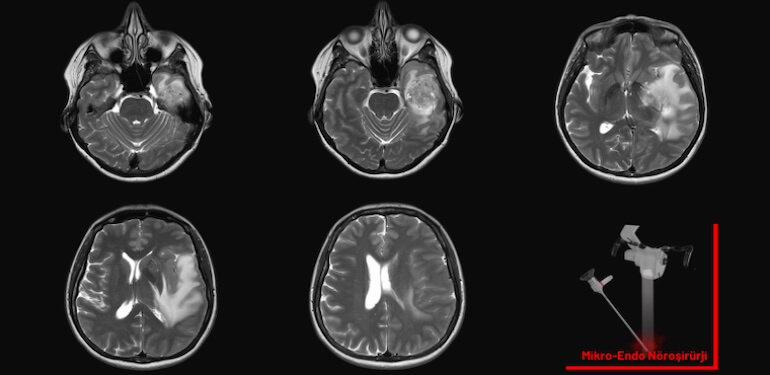

Ameliyat öncesinde ileri görüntüleme yöntemleri (MR, BT) ve nörolojik muayeneler ile tümörün tipi, yeri ve boyutu belirlenir. Aynı zamanda hastanın genel sağlık durumu detaylı olarak değerlendirilir. Bu süreç, ameliyat planlamasının temelini oluşturur.

Günümüzde cerrahi güvenliği artıran pek çok teknolojik yenilik mevcuttur. Nöronavigasyon, intraoperatif MR (iMRI) ve robotik cerrahi sistemleri (örneğin ROSA) sayesinde cerrah, tümörü daha net görebilir ve sağlıklı dokulara zarar vermeden müdahale edebilir. Bazı merkezlerde ameliyat sırasında hızlı genetik analizler de yapılabilmektedir.

Minimal İnvaziv Yaklaşımlar

Klasik açık ameliyatlara alternatif olarak geliştirilen minimal invaziv cerrahi teknikler, küçük kesilerle büyük işler başarabilmektedir. Bu teknikler, iyileşme sürecini hızlandırır, hastanede kalış süresini azaltır ve estetik açıdan avantaj sağlar.